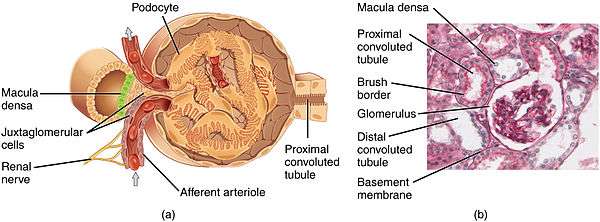

Structure

The glomerulus is a tuft of small blood vessels called capillaries located within Bowman's capsule within the kidney.[1] Between the capillaries and Bowman's capsule lies the mesangium. Blood enters the capillaries of the glomerulus by a single arteriole called an afferent arteriole and leaves by an efferent arteriole.[2] The capillaries are lined by a layer of cells (an endothelium) that has a unique structure, allowing blood components to be filtered, and resulting ultimately in the formation of urine.

Blood supply

A glomerulus receives blood from a single artery called the "afferent artery". The afferent artery is a branch of an interlobular artery in the cortex of the kidney.[1] Contraction or relaxation of the artery can affect the pressure of capillaries in the glomerulus, and consequently the filtration of blood. Sympathetic nervous system action as well as hormones can also impact glomerular filtration rate by modulating afferent arteriole diameter. As an example, one study involving rats found that having narrowed afferent arterioles contributed to the development of increased blood pressure.[3]

The juxtaglomerular apparatus allows specialized cells to monitor the composition of the fluid in the distal convoluted tubule and adjust the glomerular filtration rate.

Lining

Capillaries of the glomerulus are lined by endothelial cells. These contain numerous pores (called fenestrae) 50–100 nm in diameter.[4] Unlike those of other capillaries with fenestrations, these are not spanned by diaphragms.[4] These pores allow for the free filtration of fluid, plasma solutes and protein. However they are not large enough that red blood cells can be filtered.

The glomerulus has a basement membrane consisting mainly of laminins, type IV collagen, agrin and nidogen, which are synthesized and secreted by both endothelial cells and podocytes. These form a membrane 250–400 nm in thickness, which is thicker than basement membranes in other types of tissue. The effects of mutations in the constituents of the glomerular basement membrane suggest that it plays a role in the permeability and selectivity of the filtration barrier to large molecules, such as albumin.[5]

The side of the basement membrane that faces outwards from the capillary is lined with folds called podocytes. These are themselves lined with folds of cytoplasm called foot processes, or pedicles.[4] These control the filtration of proteins from the capillary lumen into Bowman's space. The space between adjacent podocyte foot processes is spanned by a slit diaphragm formed by several proteins including podocin and nephrin. In addition, foot processes have a negatively charged coat (glycocalyx) that limits the filtration of negatively charged molecules, such as serum albumin.

Mesangium

The space between the cells of a glomerulus is occupied by intraglomerular mesangial cells. They are not part of the filtration barrier but are specialized pericytes that participate indirectly in filtration by contracting and reducing the glomerular surface area, and therefore filtration rate, in response mainly to stretch.

Blood drainage

Blood is carried out of the glomerulus by an efferent arteriole instead of a venule, as is observed in most other capillary systems.[2] This provides tighter control over the blood flow through the glomerulus, since arterioles dilate and constrict more readily than venules, owing to arterioles' larger smooth muscle layer (tunica media).

Efferent arterioles of juxtamedullary nephrons, the 15% of nephrons closest to the medulla, send straight capillary branches that deliver isotonic blood to the renal medulla. Along with the loop of Henle, these vasa recta play a crucial role in the establishment of the nephron's countercurrent exchange system.

The efferent arteriole, into which the glomerulus delivers blood, empties into an interlobular vein.

Filtrate drainage

The filtrate that has passed through the capillaries of the glomerulus enters Bowman's capsule. From there, it leaves the corpuscule by a proximal convoluted tubule and enters the collecting duct system of the nephron.[1]